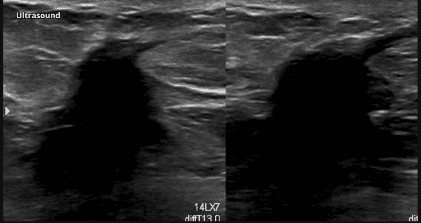

Siêu âm vú không những cho phép đánh giá hình ảnh tổn thương một cách rõ ràng mà còn cho phép đánh giá tính chất di động của tổn thương thông qua quá trình đè ép với thời gian thực (real-time). Hình ảnh siêu âm sẹo trong vú là cấu trúc hồi âm kém nguồn gốc từ mô liên kết tái tạo tăng sinh lan tỏa. Tổn thương có bờ không phân biệt, có bóng lưng. Mô sẹo xơ liên kết khi đè ép dưới đầu dò thường bị dẹt ra, làm khối hồi âm kém và bóng lưng biến mất. Đây là đặc điểm có thể dùng để phân biệt giữa u tái phát và sẹo sau phẫu thuật.

Hình 2: Hình ảnh siêu âm thấy khối hồi âm kém bờ nhiều thùy có bóng lưng.